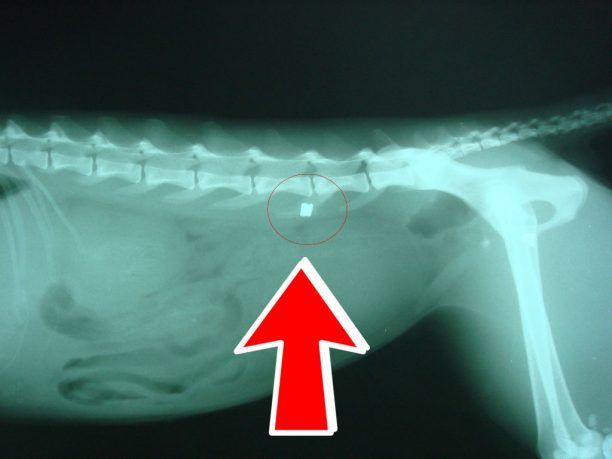

Στις 17 Μαΐου κάτοικος του χωριού Θυμιανά στην Χίο εντόπισε παράλυτη την γάτα που βλέπετε. Επικοινώνησε με τον Φιλοζωικό Σύλλογο Χίου (Φ.Σ.Χ.) εθελοντής του οποίου μετέφερε το ζώο σε κτηνίατρο.

Εκεί η ακτινογραφία έδειξε ότι το γατί είχε χτυπηθεί με αεροβόλο όπλο στην σπονδυλική στήλη. Ο κτηνίατρος Βαλάντης Μάντικας αφαίρεσε χειρουργικά το σφαιρίδιο και το ζώο παρέμεινε για νοσηλεία όμως δυστυχώς το πίσω μέρος του σώματος του έχει νεκρωθεί. Από τον Φ.Σ.Χ. έγινε καταγγελία στο Α.Τ. Χίου και γι’ αυτό το έγκλημα. Αν γνωρίζετε τον δράστη καταγγείλτε τον στην Αστυνομία του νησιού ή επικοινωνήστε με τον Φ.Σ.Χ. τηλέφωνο: 6980470162.